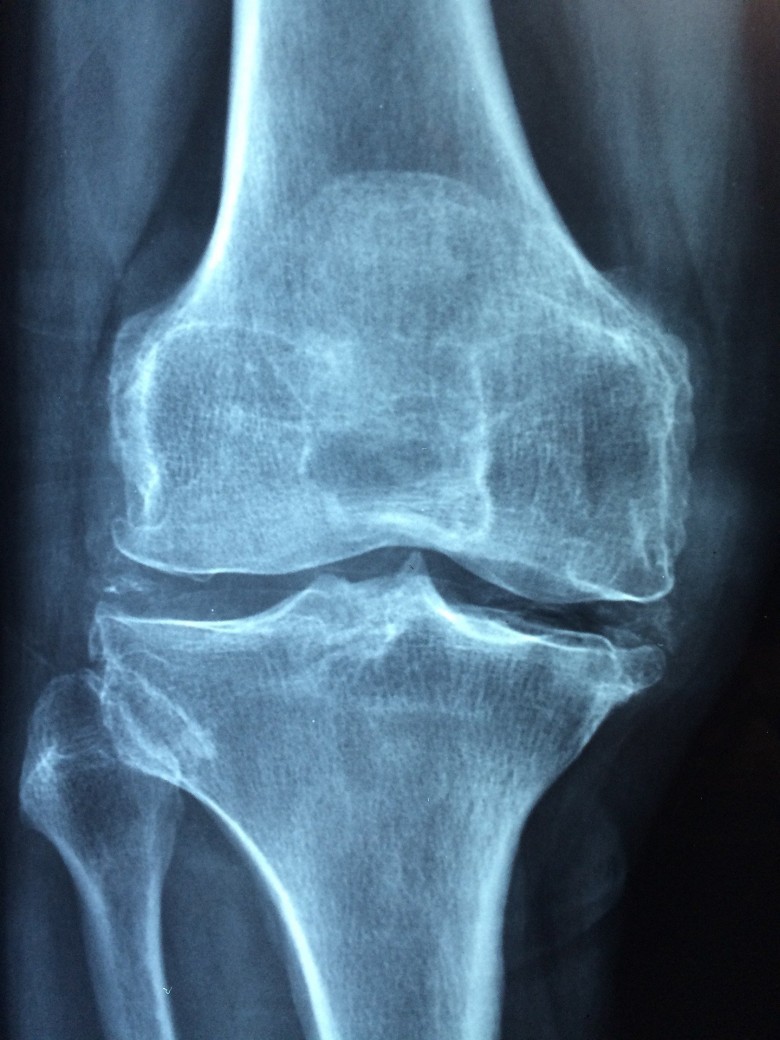

Du Huo Ji Sheng Wan for rheumatic arthritis, rheumatoid arthritis, rheumatic back pain, and sciatica

Du Huo Ji Sheng Wan is a popular herbal medicine in China. It is highly recommended as a cure for rheumatic arthritis, rheumatic back pain, rheumatoid arthritis and sciatica. This herbal formula was developed after long term thorough research and used to enhance the circulation of blood in the body. It also assists in regulating the skeletal system of the body in a healthy way. The herbal therapists of China call Du Huo Ji Sheng Wan a biologically active medicine that is pure and is of the best quality. Its major function is to keep warm and nourishing the flow of Qi in the body. It also reinforces the bones and muscles and regulates the flow of blood in the veins, arteries and tissues.

Du Huo Ji Sheng Wan is also applicable for the stiffness of legs and waist. It is suggested for the patients who are suffering from spasmodic pain in bones and muscles, weakness of lower extremities and knees and for pain in the knees and back. All the ingredients that are used in the manufacturing of Du Huo Ji Sheng Wan are the herbs and roots of very good quality with excellent medicinal value. The major ingredients that are used in the production of Du Huo Ji Sheng Wan include Pubescent Angelica, Codonopsis, Lorunthus, Cortex Eucommia E, and Poria.